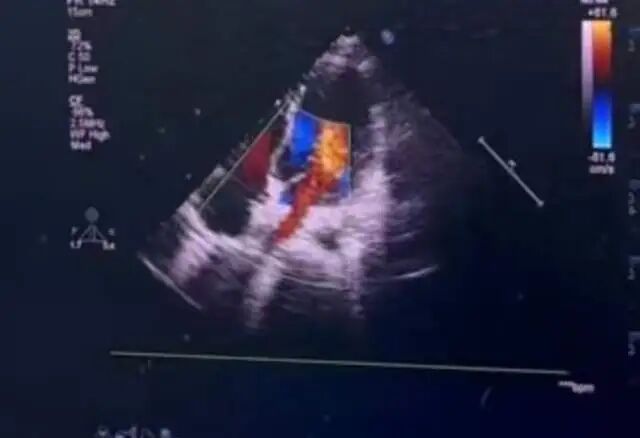

针对低龄患儿血管纤细、心脏结构未发育完全的特点,手术团队采用以超声引导为主、极少射线辅助的精准操作模式。术中超声全程实时清晰呈现心脏缺损位置、封堵器释放与贴合状态,在有效避免传统X射线对患儿辐射影响的同时,实现了40分钟内封堵器精准植入,且术后无残余分流。

▲封堵器植入术后超声心动图血流评估